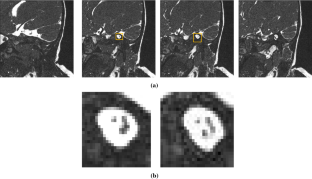

The main scope of this research is to present an automatic method to detect and segment the IAC and its nerves like the facial nerve, cochlear nerve, inferior vestibular nerve, and superior vestibular nerve. To address this issue, we propose a Mask R-CNN approach driven with U-net to detect and segment the IAC and its nerves. The Mask R-CNN with its backbone network of the RESNET50 model learns a background-based localization policy to produce an actual bounding box of the IAC. Furthermore, the U-net segments the structure related information of IAC and its nerves by learning its features.

The proposed method was experimented on clinical datasets of 50 different patients including adults and children. The localization of IAC using Mask R-CNN was evaluated using Intersection of Union (IoU), and segmentation of IAC and its nerves was evaluated using Dice similarity coefficient.

The localization result shows that mean IoU of RESNET50, RESNET101 are 0.79 and 0.74, respectively. The Dice similarity coefficient of IAC and its nerves using region growing, PSO and U-net method scored 92%, 94%, and 96%, respectively. The result shows that the proposed method outperform better in localization and segmentation of IAC and its nerves. Thus, AI aids the radiologists in making the right decisions as the localization and segmentation of IAC is accurate.